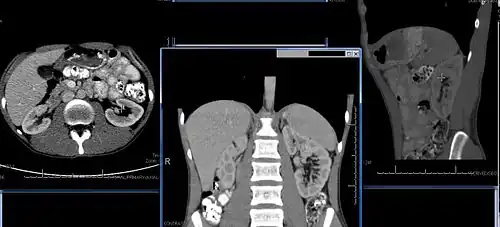

Chronic kidney disease (CKD) has been recognized as a leading public health problem worldwide. The global estimated prevalence of CKD is 13.4%, and patients with kidney failure needing renal replacement therapy are estimated between 5 and 7 million.[6] Procedures used in the management of kidney disease include chemical and microscopic examination of the urine (urinalysis), measurement of kidney function by calculating the estimated glomerular filtration rate (eGFR) using the serum creatinine; and kidney biopsy and CT scan to evaluate for abnormal anatomy. Dialysis and kidney transplantation are used to treat kidney failure; one (or both sequentially) of these are almost always used when renal function drops below 15%. Nephrectomy is frequently used to cure renal cell carcinoma.

Imaging

Renal ultrasonography is essential in the diagnosis and management of kidney-related diseases.[49] Other modalities, such as CT and MRI, should always be considered as supplementary imaging modalities in the assessment of renal disease.[49]